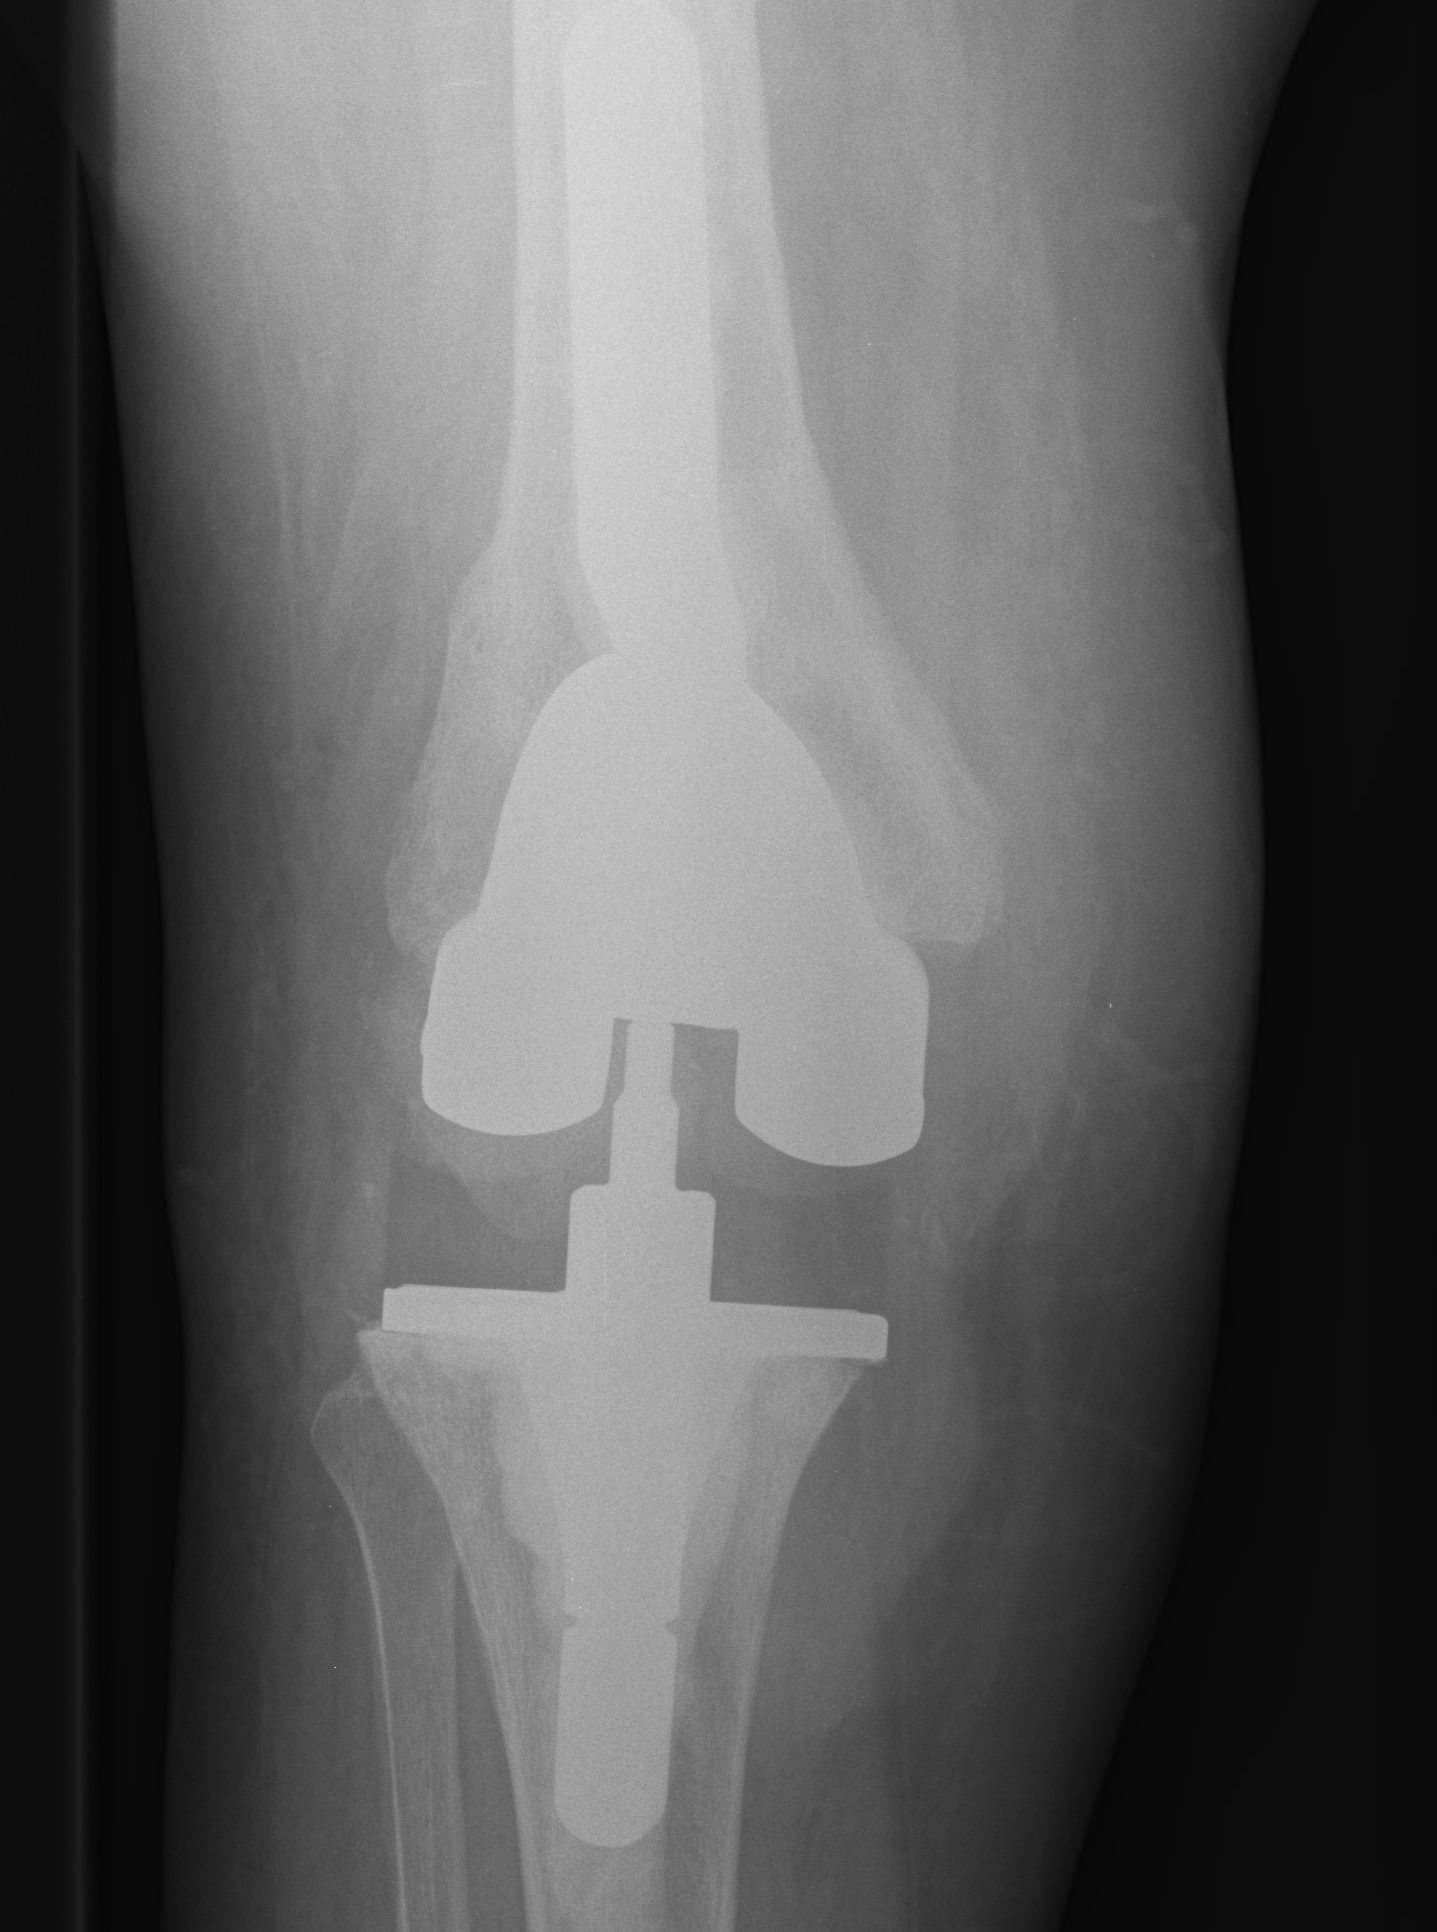

- 184 cemented revision TKR with press fit stems

- significant bone loss

10. Loosening